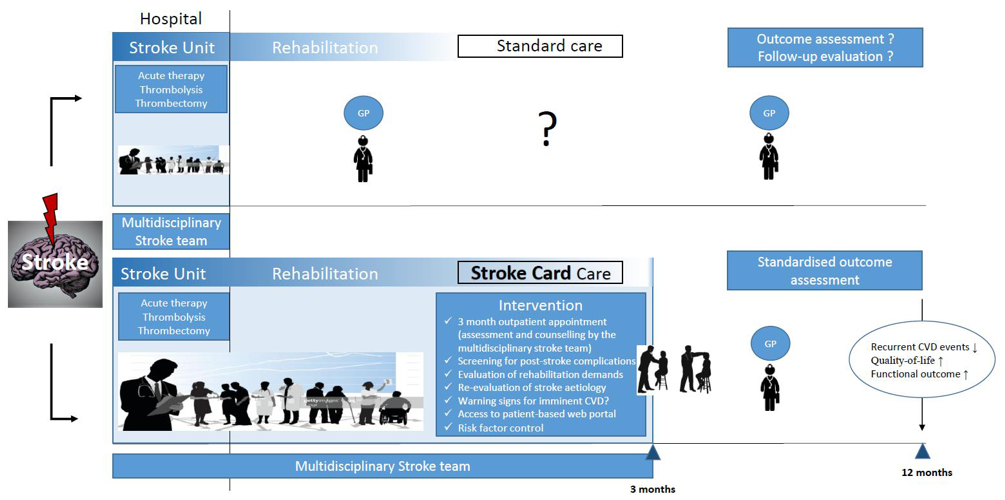

The Clinical Epidemiology research group oversees and analyses large-scale consortia (Proof-ATHERO: 90 studies, 150k participants) and individual studies (e.g. Bruneck Study, STROKE-CARD trial, School-SARS-CoV-2 Study – commonly known as the “Gurgel Study”), using cutting-edge methodology in epidemiology and data science.

The research competences of the Stroke research group include acute stroke therapy, post-stroke disease management, stroke rehabilitation, cervical artery dissection, vascular biology and ageing, and atherosclerosis research including mechanisms of early vascular ageing in the young. Funding is provided by the FFG (COMET Centre and K-Project VASCage), FWF, Standortagentur Tyrol, Reformpool, BHF, MRC, NRC, Diabetes UK, Leducq and others. The group operates a number of epidemiological studies (EVA, EVA4YOU, STROKE-CARD, STROKE-CARD Registry, Bruneck Study and ARFY) and contributes significantly to large research consortia such as ERFC, GBD and NCD.

Research Group Clinical Epidemiology

- Willeit P, Toell T, Boehme C, Krebs S, Mayer L, Lang C, Seekircher L, Tschiderer L, Willeit K, Rumpold G, Schoenherr G, Griesmacher A, Ferrari J, Knoflach M, Lang W, Kiechl S, Willeit J: STROKE-CARD care to prevent cardiovascular events and improve quality of life after acute ischaemic stroke or TIA: A randomised clinical trial. EClinicalMedicine. 2020 Jul 28;25:100476. doi: 10.1016/j.eclinm.2020.100476

Research Group Stroke

- Willeit P, Toell T, Boehme C, Krebs S, Mayer L, Lang C, Seekircher L, Tschiderer L, Willeit K, Rumpold G, Schoenherr G, Griesmacher A, Ferrari J, Knoflach M, Lang W, Kiechl S, Willeit J; STROKE-CARD study group: STROKE-CARD care to prevent cardiovascular events and improve quality of life after acute ischaemic stroke or TIA: A randomised clinical trial. ECLINICALMEDICINE: 2020; 25:100476.